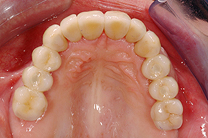

Gesamtrekonstruktionen

Fehlen in einem Kiefer alle Zähne oder sind die meisten Zähne in einem schlechten, nicht erhaltungswürdigen Zustand, ist es sinnvoll eine Gesamtrekonstruktion anzufertigen. Diese kann sowohl dental als auch implantat-getragen sein. Die Gesamtrekonstruktionen sind zeitlich wie finanziell aufwendig, bestechen aber durch ihre Ästhetik und die Langlebigkeit. Der Vorteil ist, dass viele kleine Arbeiten und Reparaturen in den nächsten Jahren wegfallen werden.